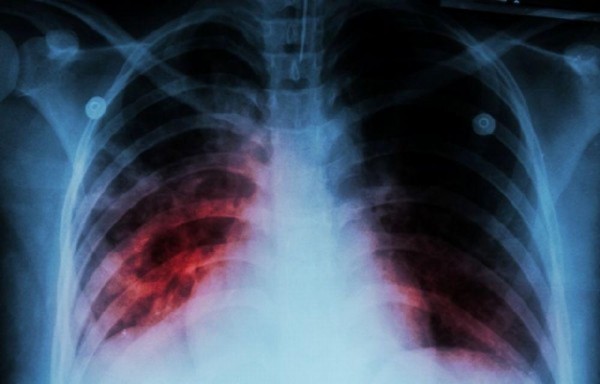

Salud. La enfermedad de tuberculosis produce: tos seca, fiebre, expectoraciones sanguinolentas y pérdida de peso

Salud. La enfermedad de tuberculosis produce: tos seca, fiebre, expectoraciones sanguinolentas y pérdida de peso.